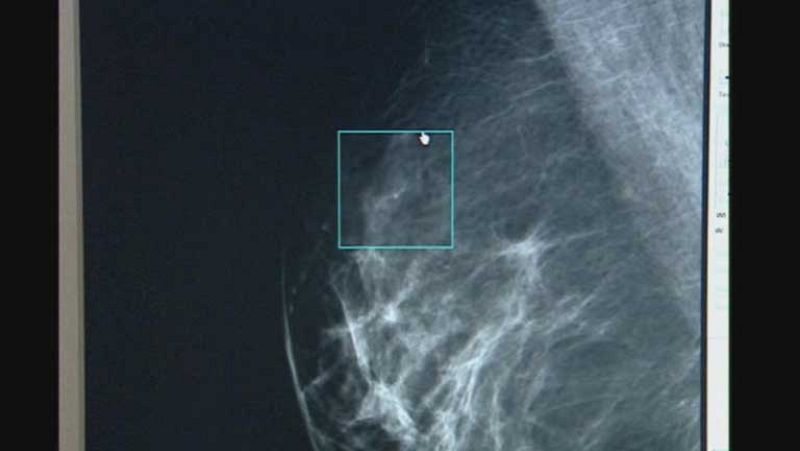

Investigadores del hospital Vall d'Hebron de Barcelona han encontrado un método para mejorar el diagnóstico de los tumores de mama más frecuentes. El nuevo sistema ayuda a perfeccionar el tratamiento y podría evitar en algunos casos la quimioterapia.